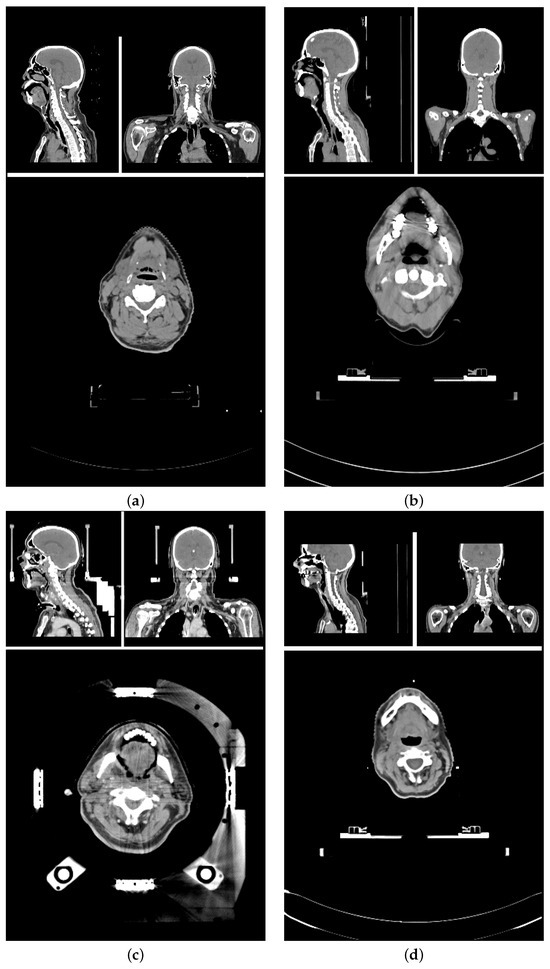

The planning CT scans for this study were aggregated from four different study cohorts. Figure 1 shows an exemplary CT scan of each cohort. All patients received radiotherapy for head and neck cancer. For each patient, there was exactly one planning CT scan considered in this study. Each CT scan consists of 90 to 220 single slices (mean: 141 ± 24) of 512 × 512 voxels each. The voxel size ranged from 0.98 × 0.98 × 2 mm 3 to 1.27 × 1.27 × 3 mm 3 .

The training data set and test data set are mutually exclusive. The training data set (86 scans) included (a) 84 in-house HNC patients from three different cohorts (varying setup, positioning, devices, and protocols) [43,44], and (b) 2 open access HNC data sets [40,41,42]. The test data set (18 scans) is curated from the same three study cohorts (14, and 4 scans, respectively). The patient selection for the test data set was based on available meta-information to best represent the variety of the data cohorts. Factors for the selections were study cohort, location of the primary tumor, gender, presence of a tracheostoma, size of nCTV, estimated age and weight of the patient.